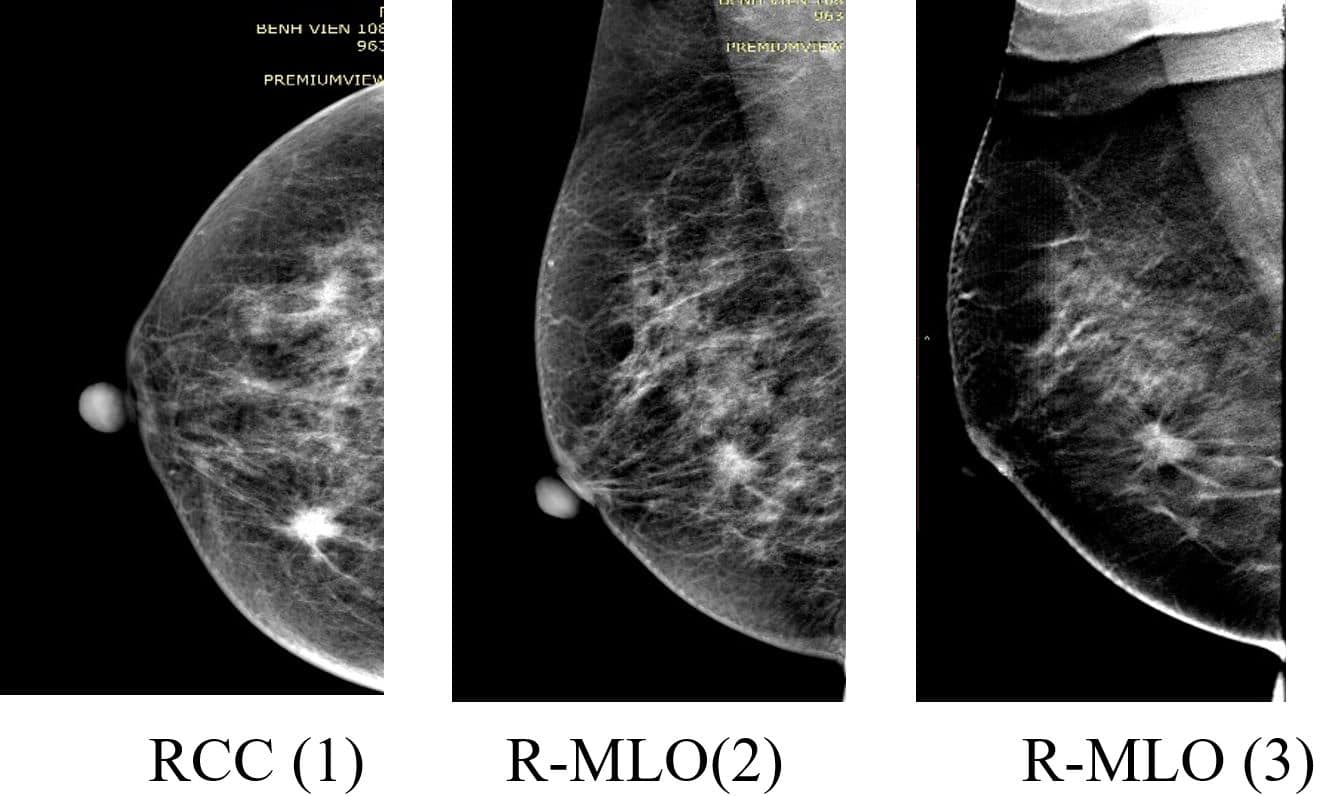

Nên tầm soát ung thư vú khoảng 5 -7 ngày sau sạch kinh. Thời điểm này nồng độ estrogen trong máu đã giảm, tuyến vú bớt giữ nước và căng hơn, quan sát hình ảnh dễ hơn. Phụ nữ nên thực hiện tầm soát ung thư vú khi bước vào độ tuổi